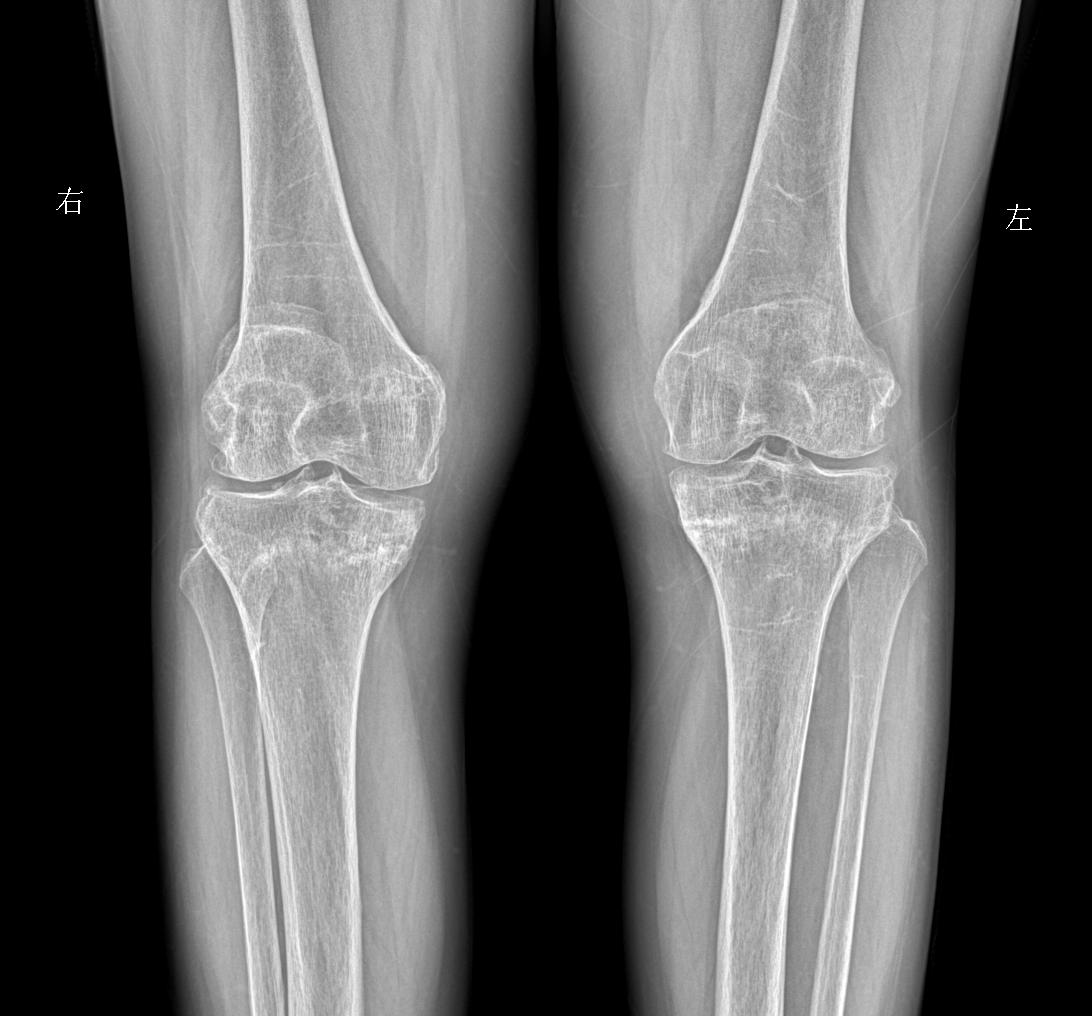

行走膝盖 脚底疼痛就诊 女69岁 考虑什么问题?

2025-06-17 01:29

老师们拍摄膝关节采取站立位还是卧位

2025-05-22 01:35